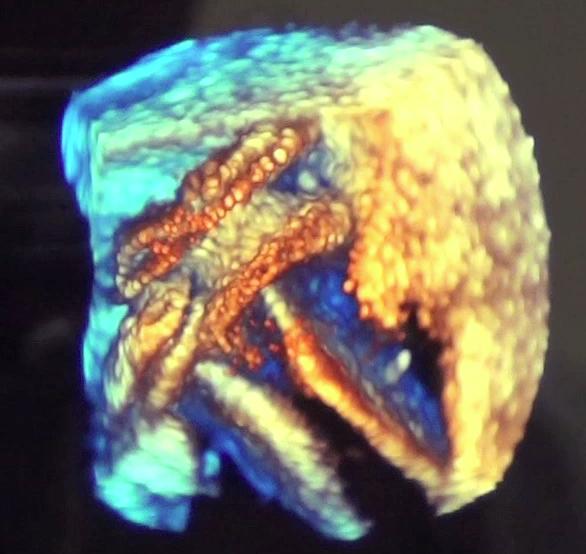

July 6, 2012 — Carestream Health showcased works-in-progress lesion management 3-D tools on its Vue PACS (picture archiving and communications system) workstation at the annual “Workstation Face-Off,” held June 18 in San Francisco as part of the annual International Symposium on Multidetector-Row CT.

With last year’s U.S. Food and Drug Administration approval of transcatheter aortic valve replacement (TAVR) and increasingly complex cath lab and hybrid operating room (OR) interventions, ultrasound is playing an increasing role in procedural guidance. This is especially true for use of 3-D/4-D transesophageal echo (TEE), which enables the more precise surgical-view visualization required for structural heart procedures, such as atrial septal defect (ASD) occluder and MitraClip deployments. These repairs would otherwise be extremely difficult to accomplish using fluoroscopy alone.